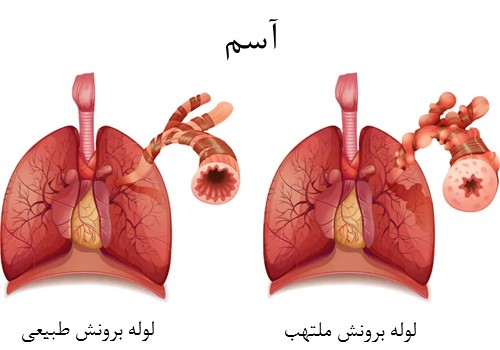

22. دانه های خشخاش برای کمک به کاهش و درمان آسم:

دانه های خشخاش عامل بسیار خوبی برای کمک به سندرم آسم است بنابراین، بسیاری از افراد، از عصاره آن استفاده می کنند تا به مشکلات تنفسی کمک کند. علاوه بر این، علائم آسم را کاهش می دهد.

23. دانه های خشخاش تنفس بهتر:

عصاره دانه های خشخاش نیز یک روش طبیعی برای ایجاد سیستم تنفسی بهتر است.این دانه ها برای جلوگیری از هر گونه ویروس و عفونت هایی که به سیستم تنفس حمله می کنند، موثر خواهد بود و در کل باعث تنفس بهتر خواهد شد.

24. دانه های خشخاش برای کمک به جلوگیری از سرفه:

از آنجا که دانه های خشخاش برای سیستم تنفسی مناسب هستند، درمان خوبی برای جلوگیری از سرفه نیز می باشند، همچنین سردرد ناشی از سرفه را نیز کاهش می دهد؛ علاوه بر این، خلط را کاهش می دهد.

29. دانه های خشخاش برای بهبود عملکرد ریه:

از آنجا که دانه های خشخاش برای سیسم تنفسی مناسب هستند، به بهبود ظرفیت ریه نیز کمک می کنند؛ علاوه بر این، می تواند ریه را در افزایش سطح اکسیژن و بهبود سیستم متابولیسم بدن بهینه کند بنابراین، راه دیگری برای افزایش میزان متابولیسم بدن می باشد.